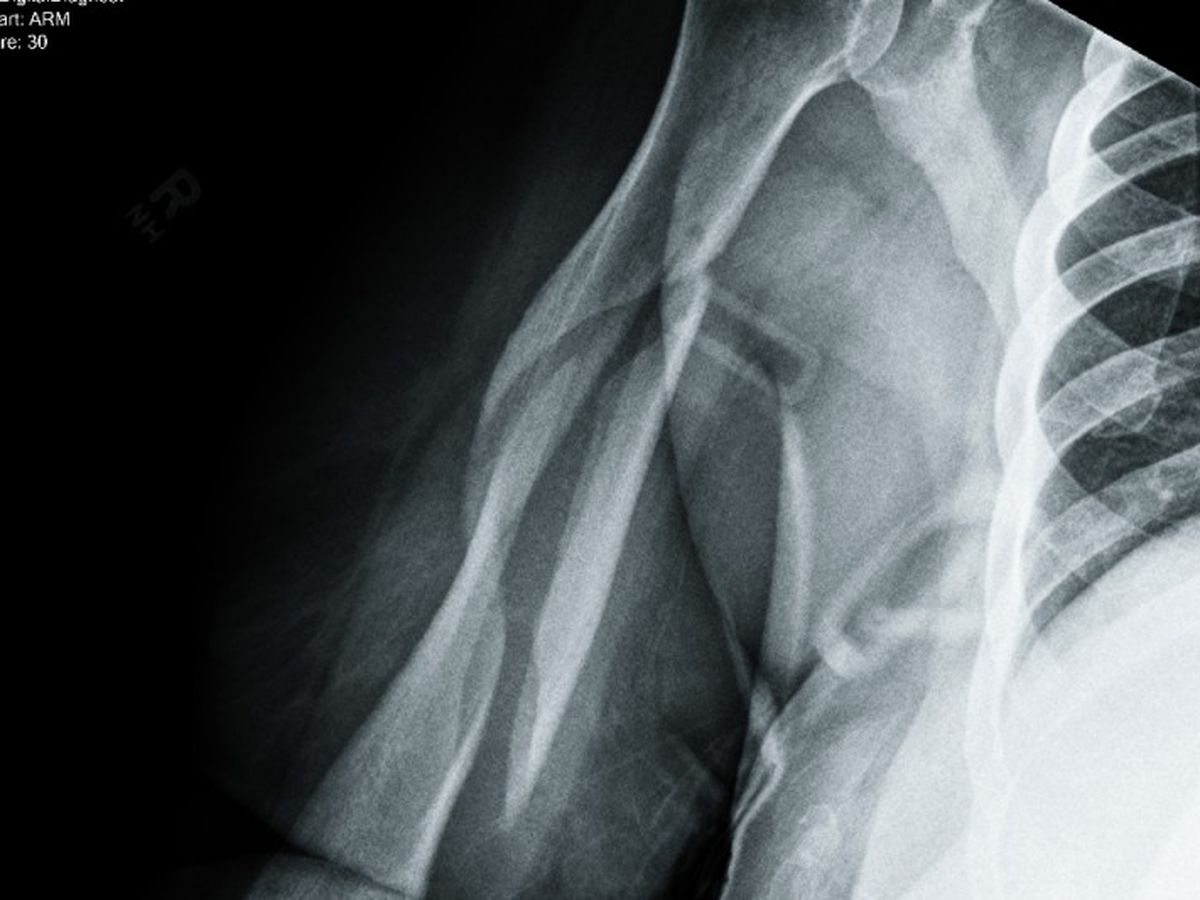

I was taken away in an ambulance to the ER . After many hours of waiting, tests, scans and an Xray, I got the bad news. My right humerous was broken in THREE places. Oh my lord! You can see the break in the X-ray photo. What do I do? Where do I go? I had no insurance. They couldn't put a cast on because of the location and nature of the break. I left the hospital with cut up clothes, stitches above my left eye, a sling and 3 pain pills!

I found a good worker comp lawyer and a real ortho specialist. On March 31st, 2015 ( my 56th birthday) I saw the doctor. The X-ray was taken. He took one look and said I needed surgery. It would never heal on its own. He classified it as a "disastrous break." In May, I had an appointment with another specialist. He only worked on upper extremities. Yup, needs surgery, with a rod and some screws and other things. My surgery was set in September of 2015. I would never have 100% use of my right arm, ever again. He didn't know how much damage the break caused, until he cut my arm open. Then a nurse took my blood pressure. It was sky high, 198/110. The doctor nealy fell over and wondered how I was still standing. Now, I needed BP meds and other tests. The insurance company denied 99% of every request. I failed the pre-op and the surgery was cancelled.